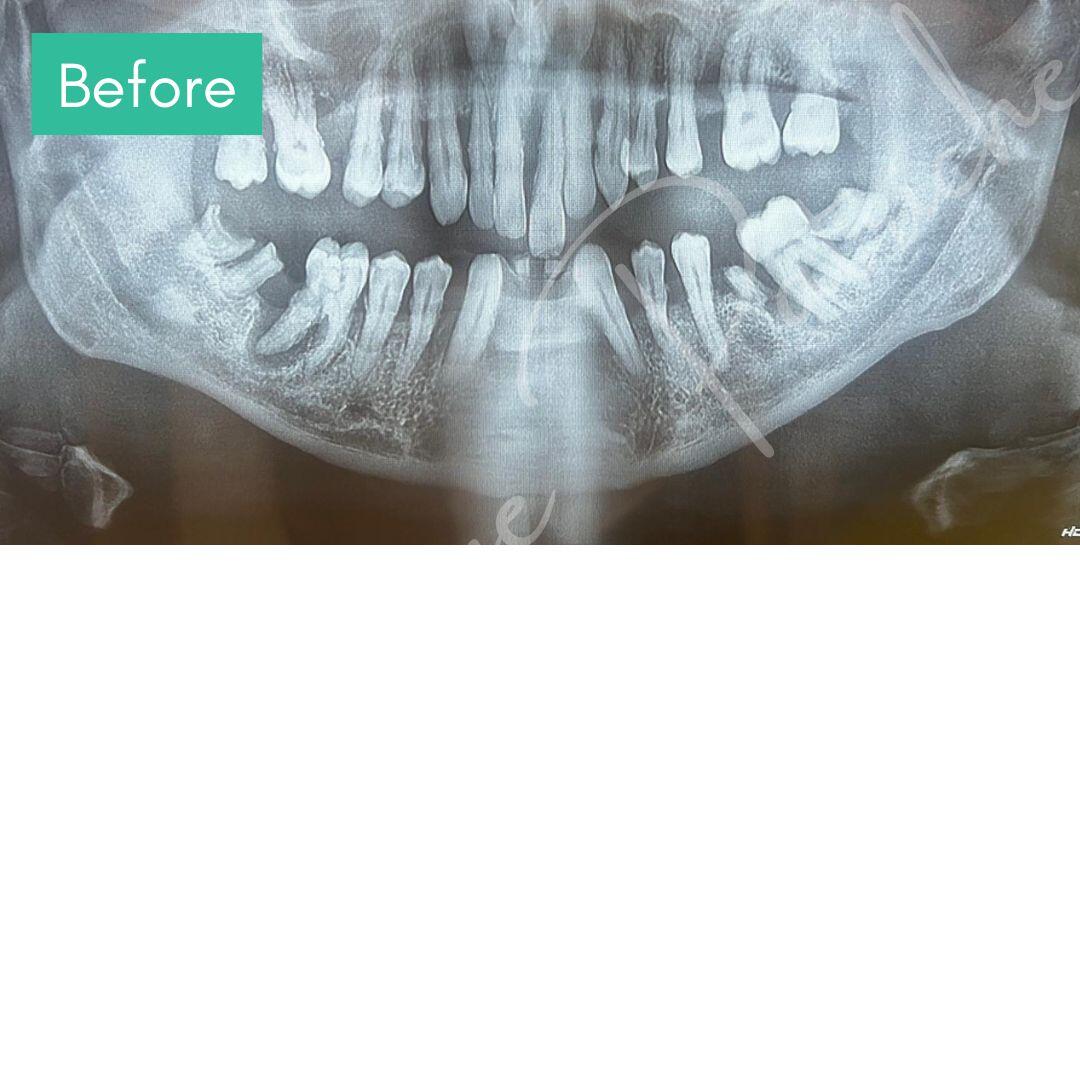

Before & After